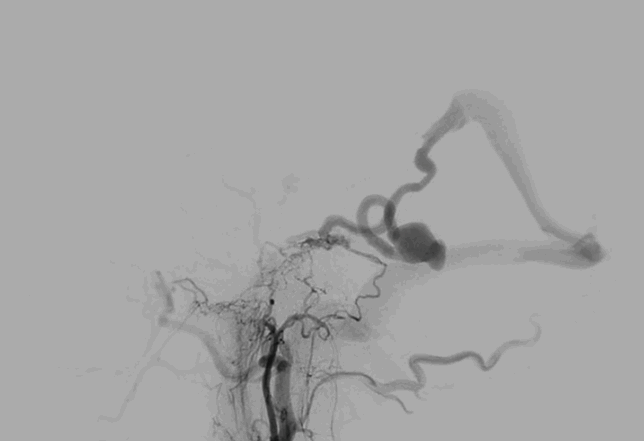

វេជ្ជបណ្ឌិតនៅនាយកដ្ឋានគ្រោះថ្នាក់ និងសង្គ្រោះបន្ទាន់របស់មន្ទីរពេទ្យ FV បានធ្វើតេស្តភ្លាមៗ ដើម្បីវាយតម្លៃស្ថានភាពអ្នកជំងឺ។ ការស្កេន MRI បង្ហាញពីការហូរឈាមនៅក្នុងខួរក្បាល។ ដោយសារការហូរឈាមក្នុងខួរក្បាលមិនត្រូវបានបង្កឡើងដោយការប៉ះទង្គិច ឬផលប៉ះពាល់ផ្សេង ការស្កេន CT តាមដានបានបញ្ជាក់ពីរោគវិនិច្ឆ័យដ៏កម្រមួយ៖ ដុំពកនៃសរសៃឈាមវ៉ែននៅខួរក្បាលទំហំ 25 មីលីម៉ែត្រ បានដាច់រហែក។ អន្តរាគមន៍ភ្លាមៗគឺសំខាន់ណាស់ ព្រោះអាយុជីវិតរបស់អ្នកជំងឺគឺស្ថិតក្នុងហានិភ័យ។

ដោយមិនស្ទាក់ស្ទើរ ក្រុមវេជ្ជសាស្រ្ដពហុជំនាញ រួមមាន នាយកដ្ឋានគ្រោះថ្នាក់ និងសង្គ្រោះបន្ទាន់ ផ្នែកថ្នាំសណ្ដំ និង សង្រ្គោះជំងឺធ្ងន់ និងផ្នែករូបភាព និងអន្តរាគមន៍រូបភាពវេជ្ជសាស្រ្ត បានធ្វើការពិគ្រោះយោបល់ជាបន្ទាន់។ លោកវេជ្ជបណ្ឌិត Huynh Huu Danh អ្នកឯកទេសកម្រិត I និងជាអ្នកជំនាញផ្នែករូបភាព និងអន្តរាគមន៍រូបភាពវេជ្ជសាស្រ្តនៅមន្ទីរពេទ្យ FV បានវាយតម្លៃករណីនេះថាជាដុំពកសរសៃឈាមដ៏កម្រដែលមានការដាច់សរសៃឈាមវ៉ែនធំ ដែលបង្កហានិភ័យនៃការហូរឈាមបន្ត និងការគំរាមកំហែងធ្ងន់ធ្ងរដល់អាយុជីវិតរបស់អ្នកជំងឺ។

ជំនួសឱ្យការវះកាត់ខួរក្បាលបើកចំហរតាបែបបុរាណ វេជ្ជបណ្ឌិតបានជ្រើសរើសសម្រាប់នីតិវិធីអន្តរាគមន៍ផ្នែកសរសៃឈាមខាងក្នុងEndovascular ។ នេះគឺជាវិធីព្យាបាលកម្រិតខ្ពស់ទំនើប និងរាតត្បាតតិចតួចដែលត្រូវបានគេស្គាល់ពីប្រសិទ្ធភាពខ្ពស់របស់វា ប៉ុន្តែទាមទារភាពជាក់លាក់ និងជំនាញច្បាស់លាស់។ អ្នកជំងឺត្រូវបានផ្ទេរភ្លាមៗទៅកាន់បន្ទប់ឆ្លុះសរសៃឈាម ជាកន្លែងដែលលោកវេជ្ជបណ្ឌិត Huynh Huu Danh អនុវត្តនីតិវិធីផ្ទាល់ដោយមានការគាំទ្រពីប្រព័ន្ធ Digital Subtraction Angiography (DSA)។

លោកវេជ្ជបណ្ឌិត Danh បានពន្យល់ថា ដោយសារតែទីតាំងរបស់Aneurysm ពិបាកចូលទៅដល់ គាត់ត្រូវតែរុករកតាមបំពង់តាមសរសៃឈាមវែនជំនួសឱ្យសរសៃឈាមអារទែ។ លោកវេជ្ជបណ្ឌិត Danh បានប្រៀបធៀបថា “ប្រសិនបើការអន្តរាគមន៍តាមសរសៃឈាមអារទែគឺដូចជាការបើកបរលើផ្លូវស្រួលរលួនមានក្រាលកៅស៊ូ តែការធ្វើអន្តរាគមន៍តាមសរសៃឈាមវែនគឺដូចជាការឆ្លងកាត់ផ្លូវរដិបរដុប និងផ្លូវខ្យល់បោកបក់ខ្លាំង ដែលអាចផ្តល់ហានិភ័យខ្ពស់និងផលវិបាក”។

តាមរយៈស្នាមវះតូចមួយនៅភ្លៅ លោកវេជ្ជបណ្ឌិត Danh បានធ្វើអន្តរាគមន៍ដោយប្រុងប្រយ័ត្ននូវបំពង់ និងខ្សែមីក្រូ-មគ្គុទ្ទេសក៍តាមរយៈសរសៃវ៉ែន ដើម្បីឈានទៅដល់កន្លែងដាច់សរសៃឈាមក្នុងខួរក្បាល។ សរុបចំនួន 12 ខ្សែ (លួសដែក) ត្រូវបានដាក់នៅខាងក្នុងរន្ធសរសៃឈាមដើម្បី “បំណះ” តំបន់ដែលខូចនិងរារាំងលំហូរឈាមតាមរយៈការធ្លាយ។